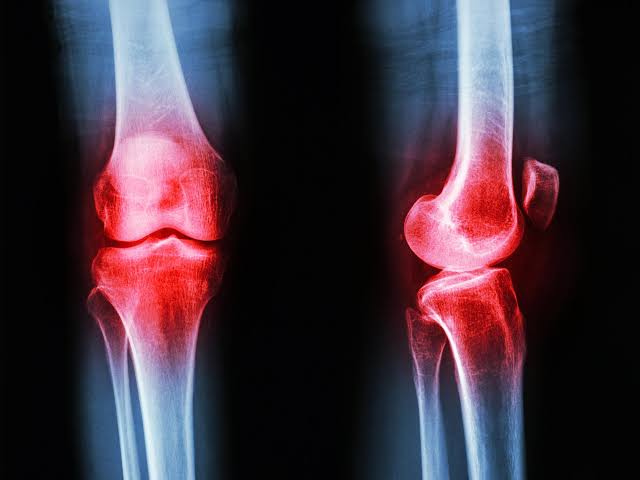

Researchers have uncovered a previously unobserved presence of the GLP-1 hormone in the joints of arthritis patients.